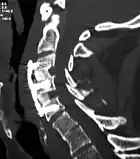

![]() X-rays of anterior cervical discectomy and fusion, C5C6 and C6C7. Lateral view. | |

To prevent the vertebrae from collapsing and to increase stability, the open space is often filled with a graft. That can be a bone graft, taken from the pelvis or cadaveric bone; or an artificial implant.[4] The slow process of the bone graft joining the vertebrae together is called "fusion". Sometimes a titanium plate is screwed on the vertebrae or screws are used between the vertebrae to increase stability during fusion, especially when there is more than one disc involved.